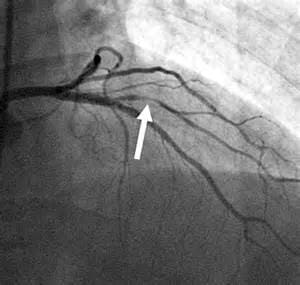

На рисунке изображена частичная непроходимость коронарной артерии.

Полученные результаты важны для врачей с точки зрения необходимости оперативного лечения. Так, например, при степени сужения просвета артерии более чем на 75% пациенту показана кардиохирургическая реперфузия (восстановление кровотока) миокарда.